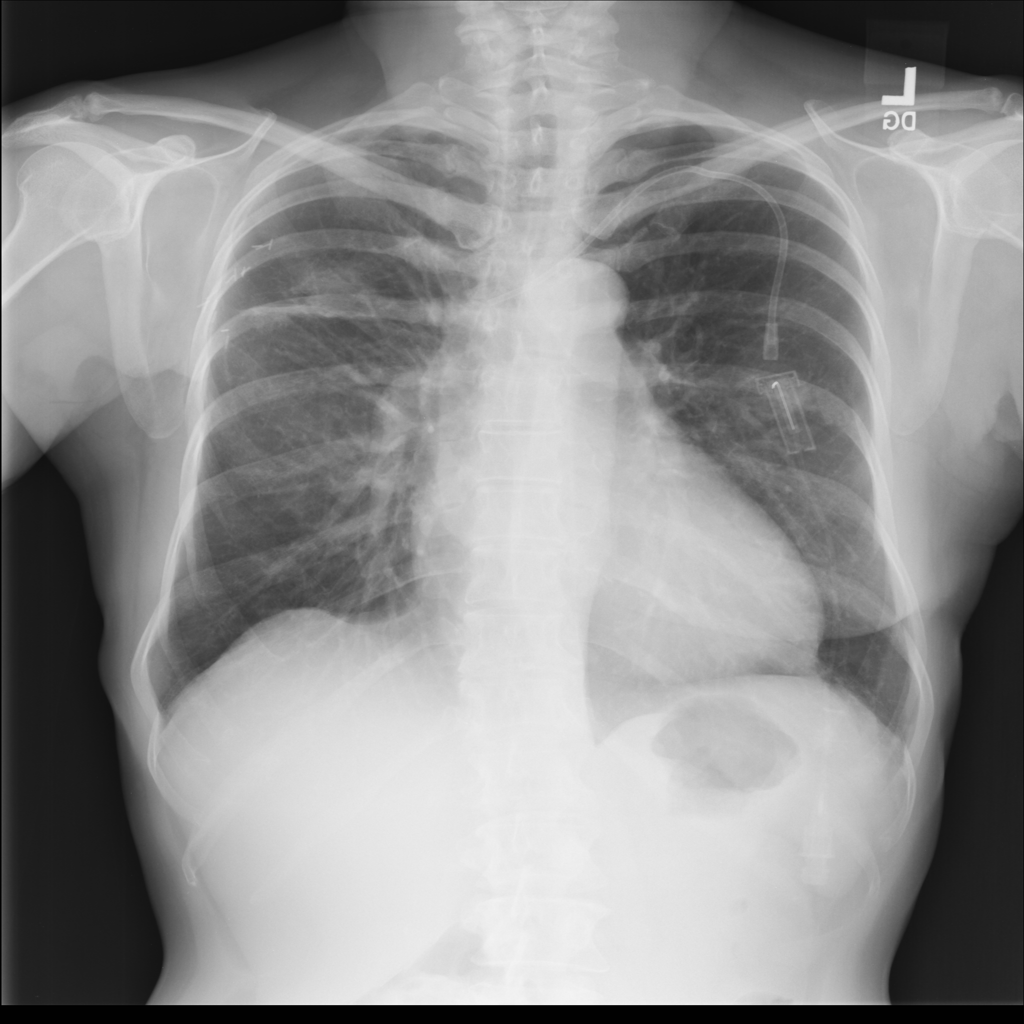

PAT-531A · IMG-006Consolidation

PAT-531A · IMG-006

PA